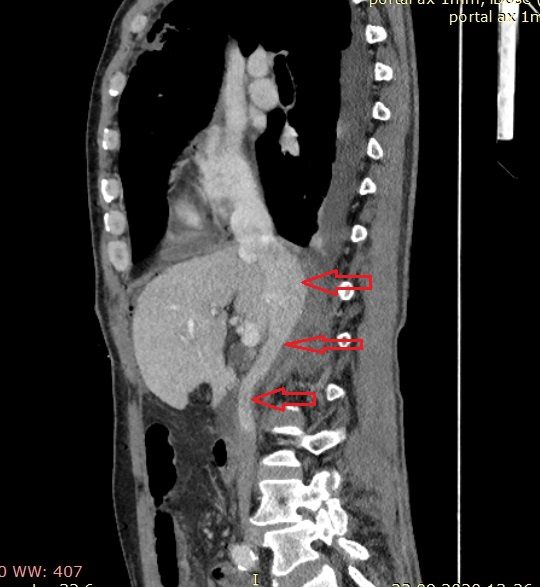

При ультразвуковом исследовании вен системы НПВ —флотирующийнеокклюзирующий опухолевый тромб супраренального, позадипеченочного отдела НПВ размером 7х2х1 см, с верхушкой на 1 см ниже устья впадения печеночных вен, с явлениями умеренной флотации (рис. 1). Надпеченочный, наддиафрамальный, инфраренальный отдел НПВ проходимы, также отмечена проходимость на всем протяжении магистральных поверхностных и глубоких вен нижних конечностей и таза.

Рис. 1. УЗ-сканограмма нижней полой вены пациента Г. Красными стрелками указан флотирующий опухолевый тромб в позадипеченочном отделе нижней полой вены.